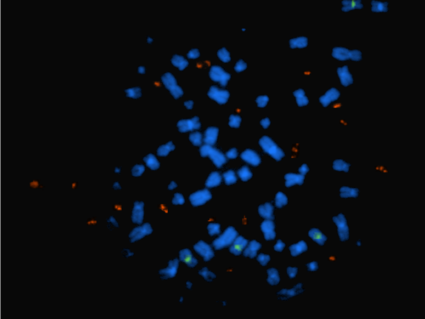

To identify potential biological mechanisms that could explain how dexamethasone impairs the immune response against tumors, the researchers focused on immune cells called T cells, which are critical for immune responses against tumors.

Treating both mouse models with dexamethasone led to a reduced number of T cells in the animals. “If there are fewer of these T cells to mount an immune response against a tumor, then it’s going to be harder for the immune system to attack a tumor and provide a therapeutic benefit for patients,” said Dr. Reardon.

The mouse studies also indicated that dexamethasone may impair the ability of T cells to generate immune responses. “The steroid may affect both the quantity and the quality of T cell responses,” Dr. Reardon noted.

A related finding—that steroids may affect the development of T cells—was reported in a 2018 study led by Mark Gilbert, M.D., chief of the NIH Neuro-Oncology Branch. Administering steroids before immunotherapy “may blunt the generation of an anti-tumor response,” these researchers concluded.